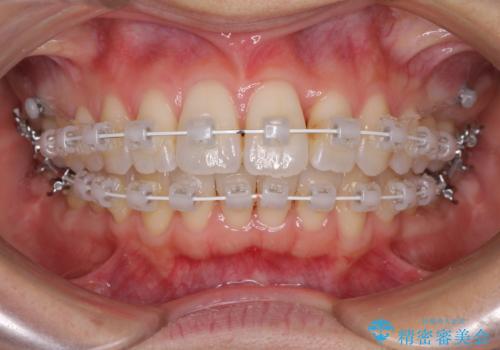

- 矯正装置

- 審美装置

上顎前歯の叢生が解消されると出っ歯になることが分かっていたので、両側奥歯付近にアンカースクリューを入れ、出っ歯を改善するためのゴムかけを行いました。

ゴムかけを頑張っていただいたので、当初の予定通り、1年強で治療を終えることができました。